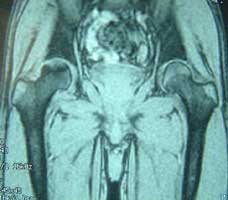

股骨头缺血性坏死MRI显示坏死区          微创手术方法,采用隧道减压刮除死骨

BMP植入,异体骨支撑,恢复形态     手术后24个月X线片,关节塌陷未加重,关节功能良好,无疼痛